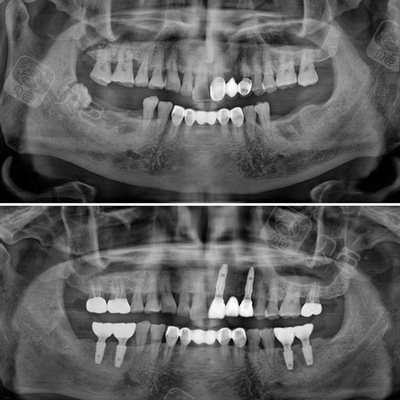

种植牙牙片

安装结束后拍摄的牙片,可见种植牙牙根的位置及骨愈合的情况.

种牙牙片欣赏

种植牙后全景片